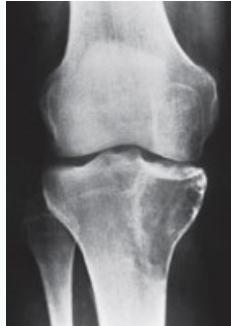

Giant-Cell Tumor

- Unknown origin:

- Giant cells abundant

- Behavior:

- One third benign

- One third locally aggressive

- One third (less) with distant metastasis

- Young adults

- Common sites:

- Around knee

- Proximal humerus

- Distal radius

Radiological Features

- Eccentric lesion:

- Radiolucent

- Soap bubble

- Abuts (adjacent) against the joint

- Thin cortex

- Margins may be clear / unclear:

- Depends on aggressiveness

- Treatment:

- Curettage & bone grafting

- More wide excision in recurrent and aggressive lesions